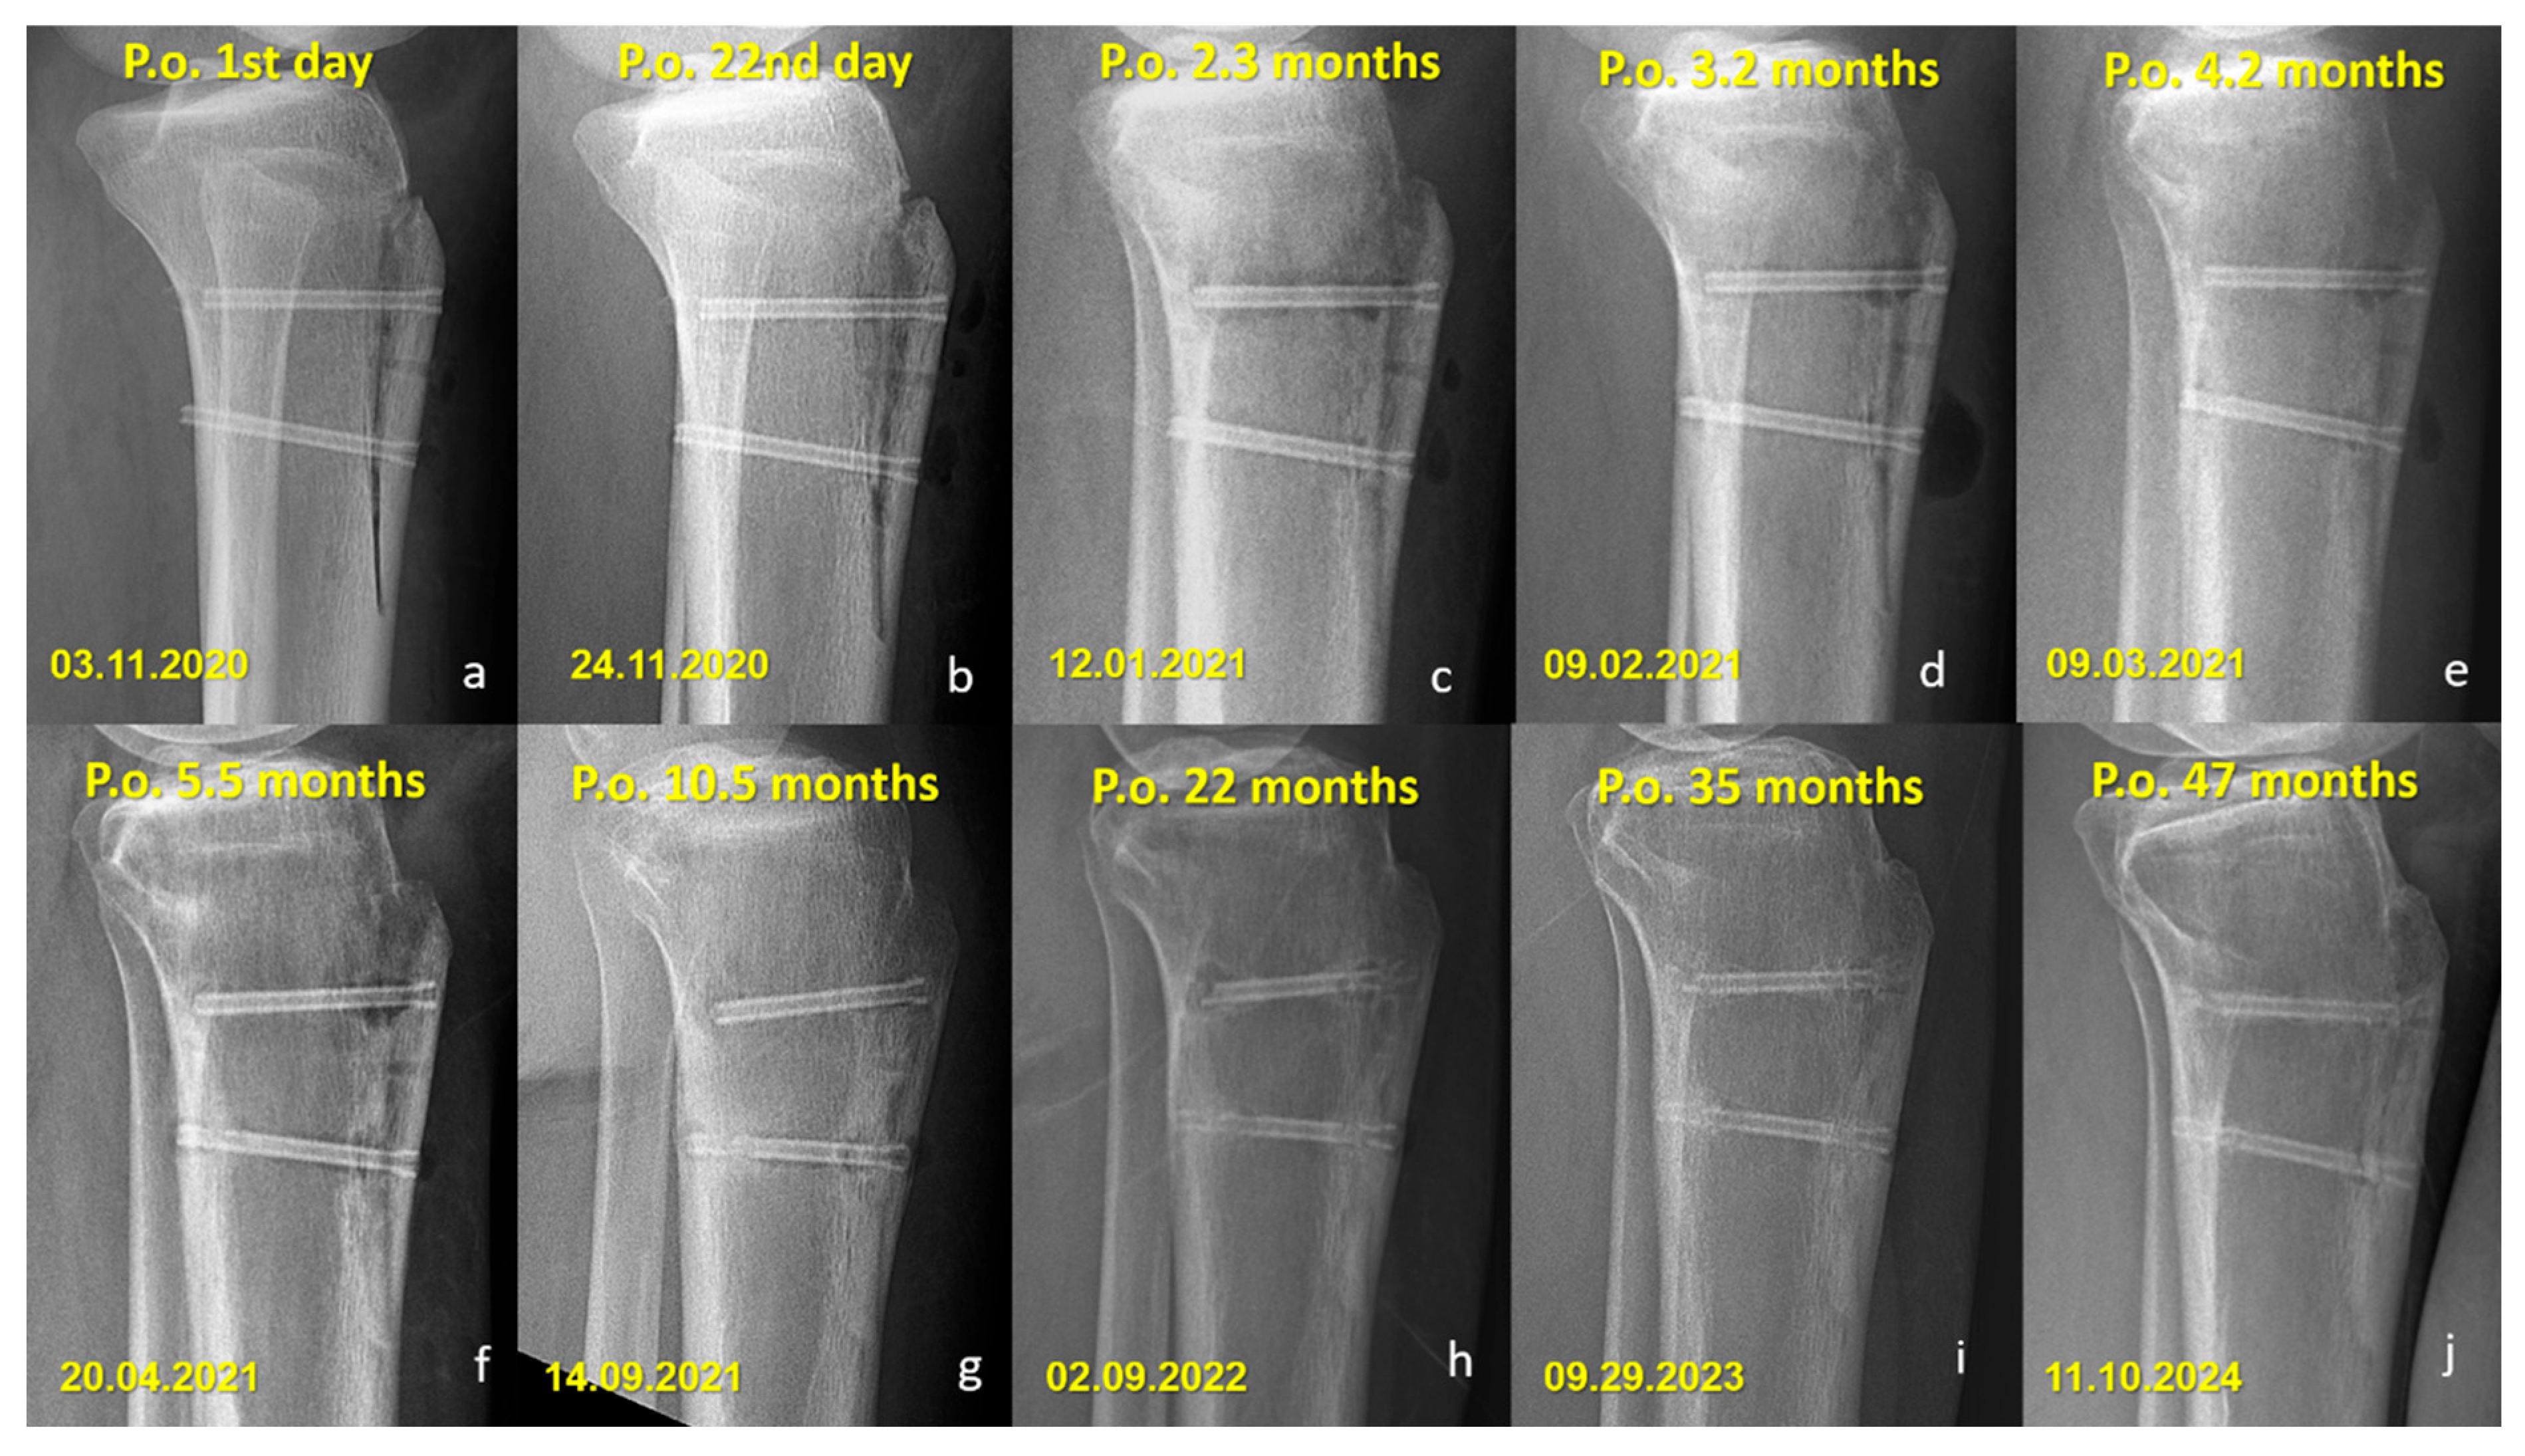

Radiographic Findings in the Mg Screw Group